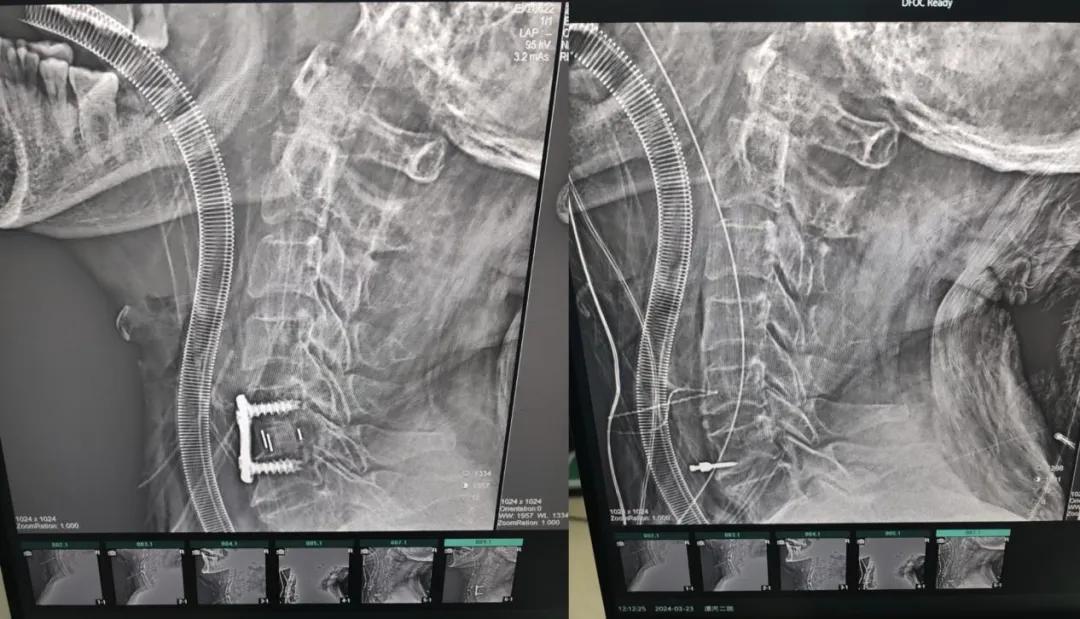

近日,70歲的馬阿姨,因摔傷后出現(xiàn)持續(xù)性頸部疼痛伴右側(cè)肢體無力、麻痛,影響日常生活。于是來到市二院神經(jīng)外科就診,經(jīng)檢查發(fā)現(xiàn):頸椎MR示:頸3/4、4/5、5/6、6/7椎間盤變性突出(中央型)并繼發(fā)性椎管變窄,頸椎退行性改變,頸5椎體水平頸髓水腫。神經(jīng)外科副主任劉沛濤根據(jù)患者癥狀、體征、影像學(xué)三者結(jié)合診斷為“脊髓型頸椎病”,考慮到患者癥狀逐漸加重、保守治療效果不佳等情況,建議盡快手術(shù)治療。

經(jīng)過縝密的術(shù)前準(zhǔn)備和手術(shù)計(jì)劃,在鄭大一附院神經(jīng)外科張風(fēng)江教授的指導(dǎo)下,神經(jīng)外科團(tuán)隊(duì)順利為患者實(shí)施“顯微鏡下頸椎前路C5/C6椎間盤切除椎間融合+內(nèi)固定術(shù)”,手術(shù)時(shí)間不到1小時(shí)。術(shù)后患者恢復(fù)情況良好。